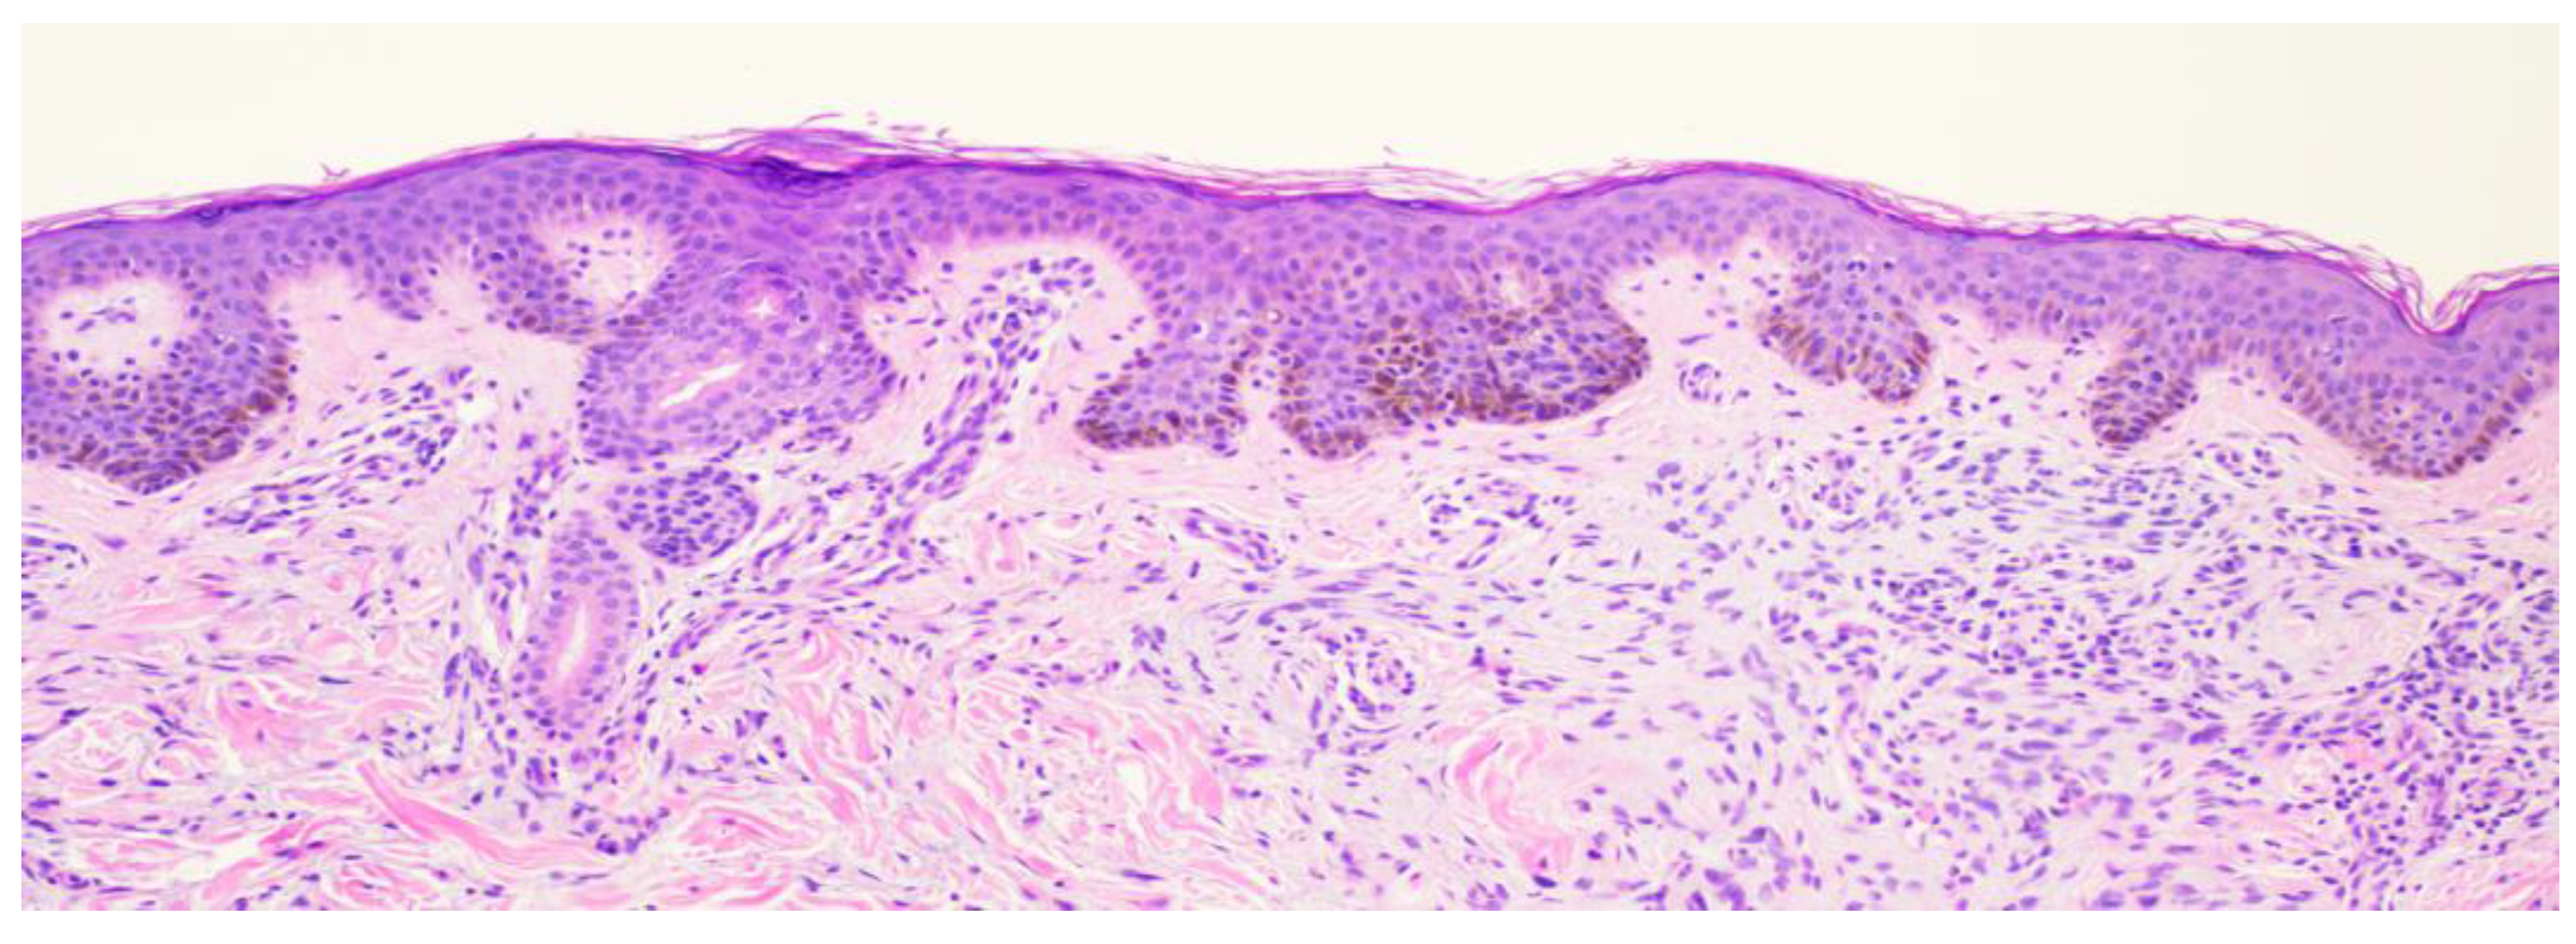

A 26-year-old male with a history of 0.4 mm malignant melanoma of the left upper extremity status post wide local excision and tenuous sun protection presented to clinic for follow-up. Exam revealed multiple scattered nevi to the head, trunk, extremities, feet, and genitalia as well as an erythematous plaque with central hyperpigmentation to the right upper arm in proximity to the shoulder (

Figure 1). A punch biopsy was obtained and revealed atypical myxoid spindle cell neoplasm and involved margins with overlying mildly atypical compound melanocytic nevus. The specimen also displayed CD34 positivity (histopathology displayed in

Figure 2,

Figure 3,

Figure 4,

Figure 5,

Figure 6,

Figure 7,

Figure 8 and

Figure 9). A diagnosis of spindle cell lipoma was reached, and wide local excision with 2 cm margins was performed and subsequent pathology revealed clear margins.

This case highlights an atypical presentation of spindle cell lipoma. The patient was a 26-year-old male with a history of malignant melanoma, who presented with an erythematous plaque on the right upper arm near the shoulder, an area that is not typically associated with SCL. Furthermore, the clinical presentation included central hyperpigmentation, which is not a common feature of SCL. The initial differential diagnosis was broad due to the atypical appearance of the lesion and CD34 positivity.

Histopathologically, the presence of an atypical myxoid spindle cell neoplasm with CD34 positivity further complicated the diagnosis. The biopsy also revealed an overlying mildly atypical compound melanocytic nevus, which is an unusual finding in SCL and raised concerns about a potential collision tumor or a misdiagnosis.